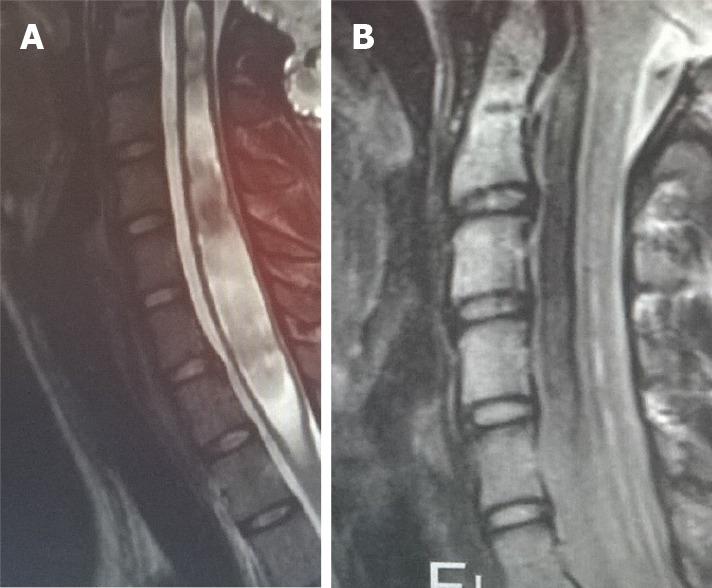

Chiari malformations encompass various radiological and clinical entities, sharing the herniation of the rhombencephalic structures through the foramen magnum as a common characteristic. They can be symptomatic or asymptomatic. The therapeutic strategies for these malformations differ on the basis of the diverse pathophysiologic processes that cause them. As Chiari malformations are caused by various pathophysiologic processes, they must be recognized promptly to select the best treatment for each single case.

Chiari畸形包括各种放射学和临床实体,其共同特征是菱脑结构通过枕骨大孔疝出。它们可以是有症状的或无症状的。这些畸形的治疗策略因导致它们的不同病理生理过程而异。由于Chiari畸形是由各种病理生理过程引起的,必须及时识别,以便为每个病例选择最佳治疗方法。